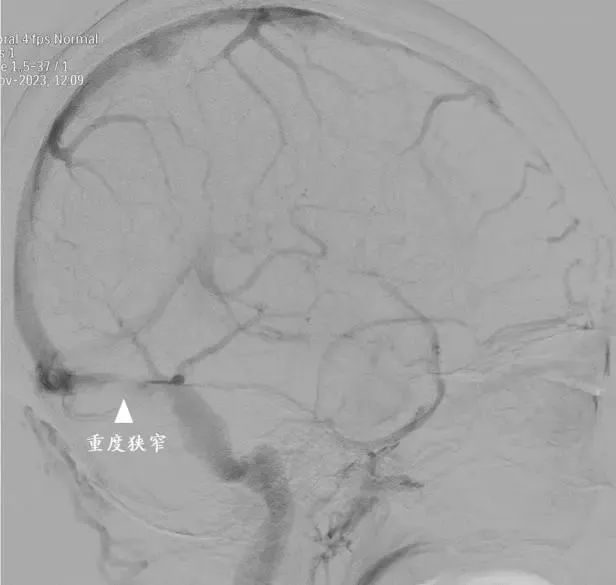

术前

经过详细的检查和评估并进行腰穿检查,异常增高的颅内压和异常的眼底表现引起了他们的高度关注——腰穿压力超过280毫米水柱,头颅磁共振静脉成像结果显示右侧横窦严重狭窄。

在血管内微创治疗手术中,神经外科副主任医师赵兵准确判断了狭窄病变的位置,精准测量了静脉窦狭窄的压力差,压力梯度超过11毫米汞柱,证实了静脉窦狭窄是导致患者痛苦的根源。手术室里,医疗团队和疾病进行着博弈,为吴女士实施静脉窦支架成形手术。手术室外,吴女士的丈夫推着婴儿车出现在手术室门口,车上躺着两个年幼的孩子,使整个手术气氛更显特殊。